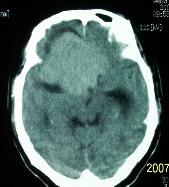

f    29岁   头闷  头晕1月余

肿瘤累及颅底前颅窝,部分层面见散在钙化,中心坏死。支持:脑膜瘤!

这么大,鞍上压迫那么厉害,梗阻也比较重没有视力及其他症状吗?从肿瘤本身表现看,支持考虑颅底脑膜瘤

肿瘤长入侧脑室,侧脑室明显扩大, 病灶边界清楚,其内可见低密度坏死区,中枢神经细胞瘤?室管膜瘤?

镰旁高密度灶,中间低密度坏死区,周围水肿较轻,支持脑膜瘤诊断,建议结合增强扫描。

右额叶底部巨大等低混杂密度肿块,边界清楚,周围水肿轻度,明显占位效应。蝶鞍扩大,部分骨质破坏。

考虑脑膜瘤,建议增强扫描进一步检查。

蝶鞍受压吸收,可以排除室管膜瘤。肿瘤最大层面不在蝶鞍可以排除垂体瘤。支持脑膜瘤